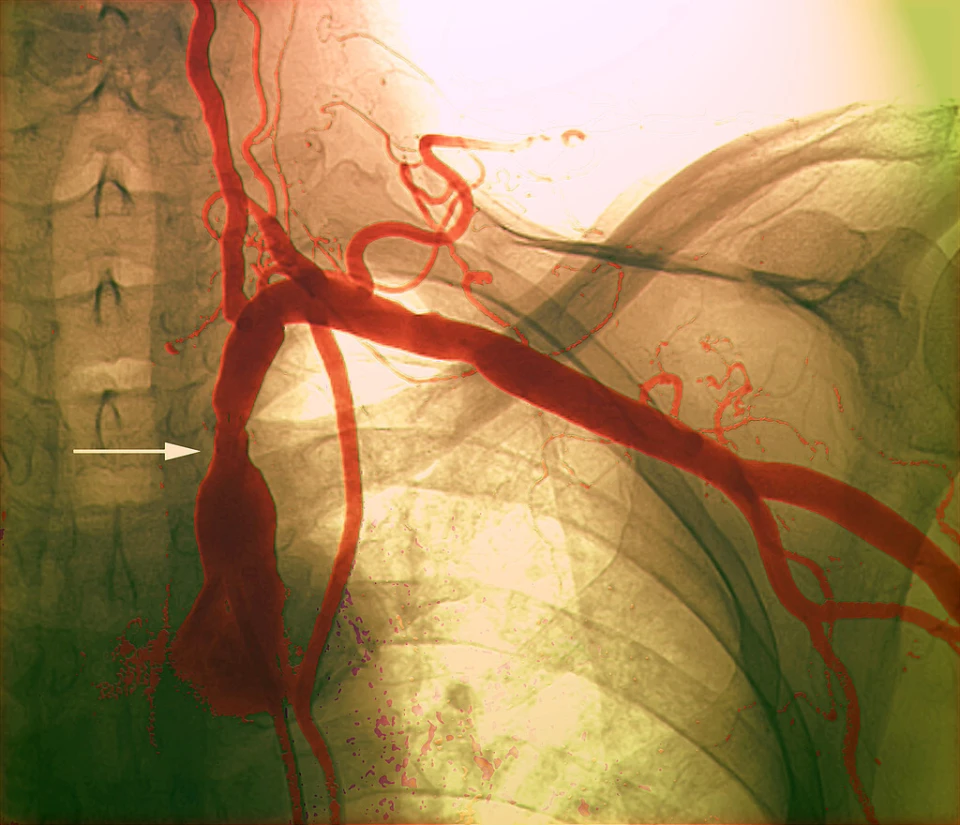

要是患者被诊断确定为急性心肌梗死,或者是处于严重心功能不全的状况,又或者是合并了多种慢性疾病,那么就必定得住院去完成造影。这些患者进行手术时所存在的风险是比较高的,有可能需要随时转变为进行急诊介入治疗。在住院的这段期间,医护人员会持续不断地监测生命体征,格外留意尿量以及肾功能的变化。

要是造影查出来血管呈现严重狭窄状况,医生已经决定要在同步植入支架的时候,这样的情形肯定是需要住院来进行治疗的。支架植入完毕后必须密切留意是不是有血栓形成、穿刺部位出现出血等之类的并发症。在住院这段期间之中,医生是会调整抗血小板药物的剂量以及种类的。